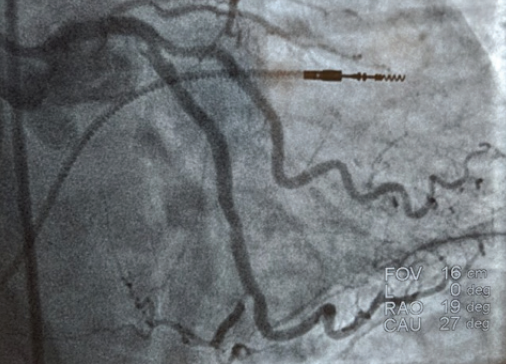

The decision was made to proceed with percutaneous coronary intervention (PCI) using an extra backup guide and a balanced middle-weight wire (BMW) to cross the lesions in the left circumflex. From the onset of the procedure, the ability to deliver a balloon and subsequent stent appears to be arduous and difficult given the tortuosity and calcification of the left circumflex. With introduction of a Guidezilla™ support catheter (Boston Scientific Corporation), a 2-mm balloon and a 2.5-mm balloon were introduced with difficulty in performing balloon angioplasty. Despite balloon angioplasty, including a high-pressure noncompliant 3.5-mm percutaneous transluminal coronary angioplasty balloon in the left main coronary artery, stent delivery was challenging and complex. The introduction of the EluNIR™ coronary stent system (Medinol Ltd., distributed by Cordis, a Cardinal Health company) allowed adequate pushability and deliverability to cover both the distal-mid–left circumflex artery with two stents. The LMCA was also stented with a 3.5-mm EluNIR™ stent, resulting in an excellent angiographic result (Figure 2). The patient’s postoperative course was uncomplicated and she was discharged home the next day.

A right radial approach using a 7-F Glidesheath™ Slender device (Terumo Interventional Systems) was selected, and heparin was administered throughout the procedure. A 7-F XB LAD guide catheter was engaged after poor mapping of the first guide, followed by a 0.014-cm BMW guidewire. Balloon angioplasty of the proximal LAD was performed with a 2.5-mm balloon. A 4- X 24-mm EluNIR™ stent was deployed in the proximal LAD. The second stent, a 3.5- X 20-mm EluNIR™, was placed in the mid-LAD with the assistance of a GuideLiner® device (Teleflex). The very distal LAD artery lesion requires predilatation with a 2-mm balloon before deployment of the third stent, a 2.5- X 24-mm EluNIR™. A 3.5-mm noncompliant balloon was used to “touch up” the middle of the stents. The procedure concluded with no complications (Figure 2).